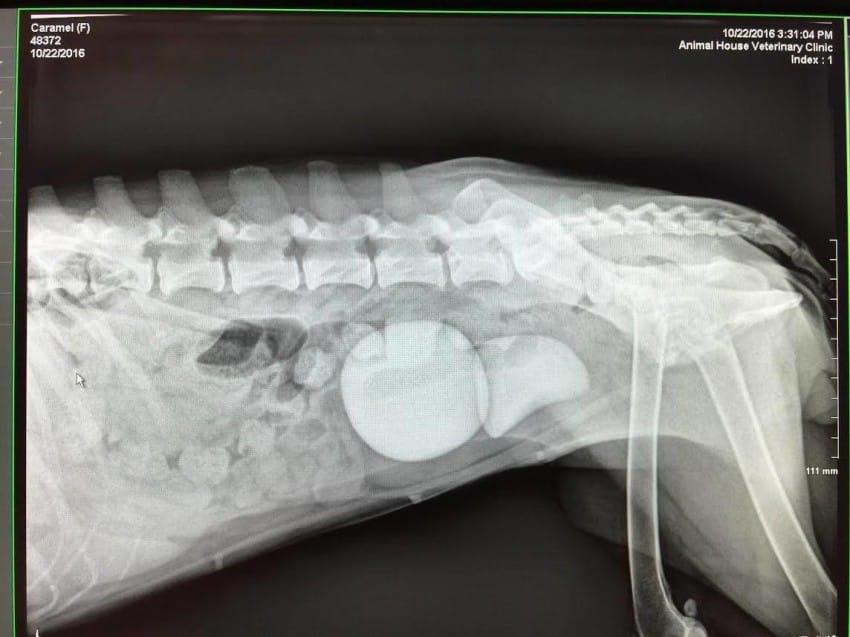

Det var först när en röntgenbild hade tagits som det gick upp för veterinären hur illa det faktiskt var.

Det vistade sig att Caramel hade två stora njurstenar i blåsan. Normalt är njurstenar ganska små, även om det kan göra mycket ont när de kommer ut genom urinvägarna. Men Caramels stenar var för stora för att komma ut den naturliga vägen.

Veterinären hade aldrig sett en så stor njursten förut. När den ligger i handen förstår man verkligen hur ont den stackars hunden måste ha haft.

Den största stenen var omkring 10 centimeter i diameter.